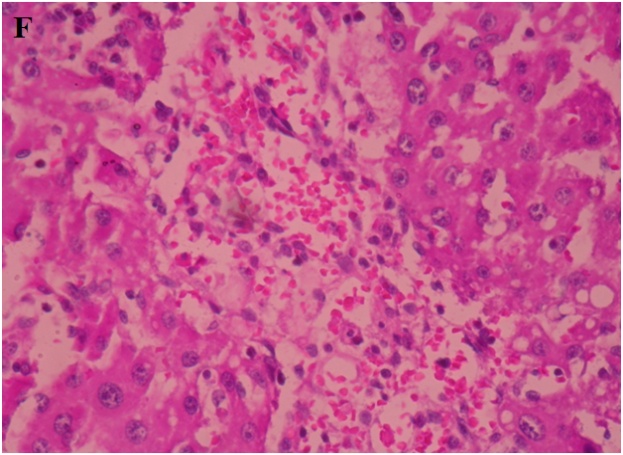

Normal hepatic cell arrangement was observed in the normal liver. Central vein, portal tract, and normal kupffer cells showed no inflammation (fig. 6A). In CCl4 treated group hepatocytes exhibited large degeneration of fatty cells, congestion of central vein and sinusoid, spotty necrosis, focal hemorrhage, ballooning and inflammation of hepatic cells (fig. 6B). In standard silymarin (100 mg/kg) treated group the hepatic globular structure was found to be normal. Mild central vein and sinusoidal congestion were noticed. Regeneration of hepatocytes was also found (fig. 6C). A4EA treated livers (50 mg/kg) exhibited normal rearrangement of hepatocytes surrounding the necrosis and fatty vacuoles (fig. 6D). A4EA treated livers (100 mg/kg) showed mild congestion of central vein and sinusoid. Mild inflammation and focal hemorrhage were seen, whereas no degeneration and ballooning of hepatic cells was observed (fig. 6E). A4nB (50 mg/kg) treated livers showed decreased inflammation of hepatocytes. Mild ballooning and degeneration of injured liver were restored (fig. 6F). A4nB (100 mg/kg) treated livers also showed regeneration of hepatocytes with mild inflammation and ballooning (fig. 6G).

F. A4nB(50 mg/kg)

Fig. 6: Histopathological sections of liver with CCl4 induced hepatotoxicity: A. Normal liver, B. CCl4 induced rat liver, C. Silymarin treated rat liver, D. A4EA (50 mg/kg), E. A4EA(100 mg/kg), F. A4nB(50 mg/kg), G. A4nB (100 mg/kg)

Normal hepatic cell arrangement was seen in the normal liver as compared to CCl4 group as hepatocytes exhibited large degeneration of fatty cells, congestion of central vein and sinusoid, spotty necrosis, focal hemorrhage, ballooning and inflammation of hepatic cells. A4EA (50 mg/kg and 100 mg/kg) showed normal rearrangement of hepatocytes round the necrosis and fatty vacuoles, with mild congestion of central vein and sinusoid. A4nB (50 mg/kg and 100 mg/kg) showed decreased inflammation of hepatocytes. Mild ballooning and degeneration of injured liver were restored. These observations showed that A4EA and A4nB (50 mg/kg and 100 mg/kg) reversed the toxic effects of CCl4 on hepatic architecture.